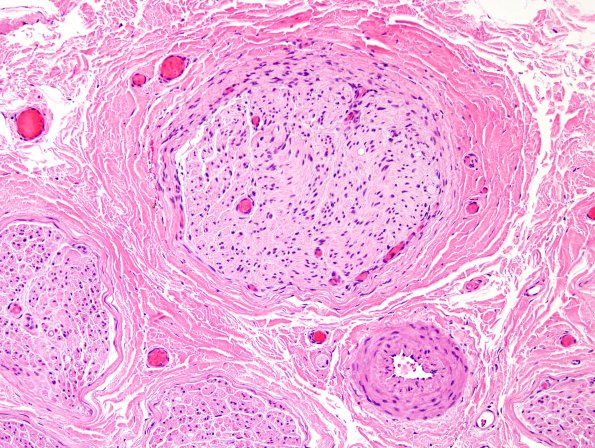

The nerve is rather unremarkable at low magnification. At higher magnification there is one fascicle in particular which is pale and apparently without myelinated axons. (H&E)